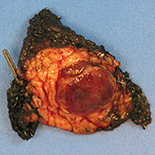

We present a case of a sporadic insulinoma in an 11-year-old boy who had episodes of self-limited drowsiness and behavior changes over a 3-month period, thought to be caused by psychological issues. Non-ketotic hypoglycemia was confirmed at our center. A fasting blood test found inappropriately elevated insulin levels during hypoglycemia, undetectable β-hydroxybutyrate, and increased C-peptide levels in line with insulin levels. Anti-insulin antibodies were negative and antidiabetic drugs untraceable. The glucagon-stimulation test was positive. Growth hormone, adrenocorticotropin hormone, and phosphorus and calcium metabolism were normal. Dual-phase computed tomography detected a lesion compatible with an insulinoma. Endoscopic ultrasound showed a homogenous lesion at the junction of the body and tail of the pancreas. Histologic analysis of a fine-needle aspiration biopsy was compatible with neuroendocrine neoplasia. Preoperatively, a fractional diet avoiding fast-absorbing carbohydrates maintained normal glucose blood levels. Enucleation was not possible, so the lesion was resected along with portions of the body and tail of the pancreas. The well-differentiated tumor measured 15 mm x 13 mm. Postoperative blood glucose levels were correct, allowing a normal diet.